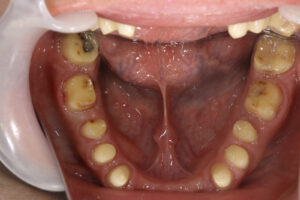

初診日 2016. 12.  (5年経過症例)

患者様の症状

1年前から他の歯科医院にて部分的な治療を受けたが、どんどん歯が悪くなって、見た目が良くない・噛めないとのことで再治療を希望された。昨日、上の前歯が自然に取れた、他の医院に行こうとしたところ知人に当医院を勧められ来院した。アングルクラスⅡであった。

治療法

全顎的に歯周病が進行し、ほとんどの歯に動揺が見られた。アングルクラスⅢで下顎前歯部に叢生が見られ、全顎の再生療法の後に、全顎的にオールセラミッククラウンを装着し、既存の被せのやり直しを行なった。